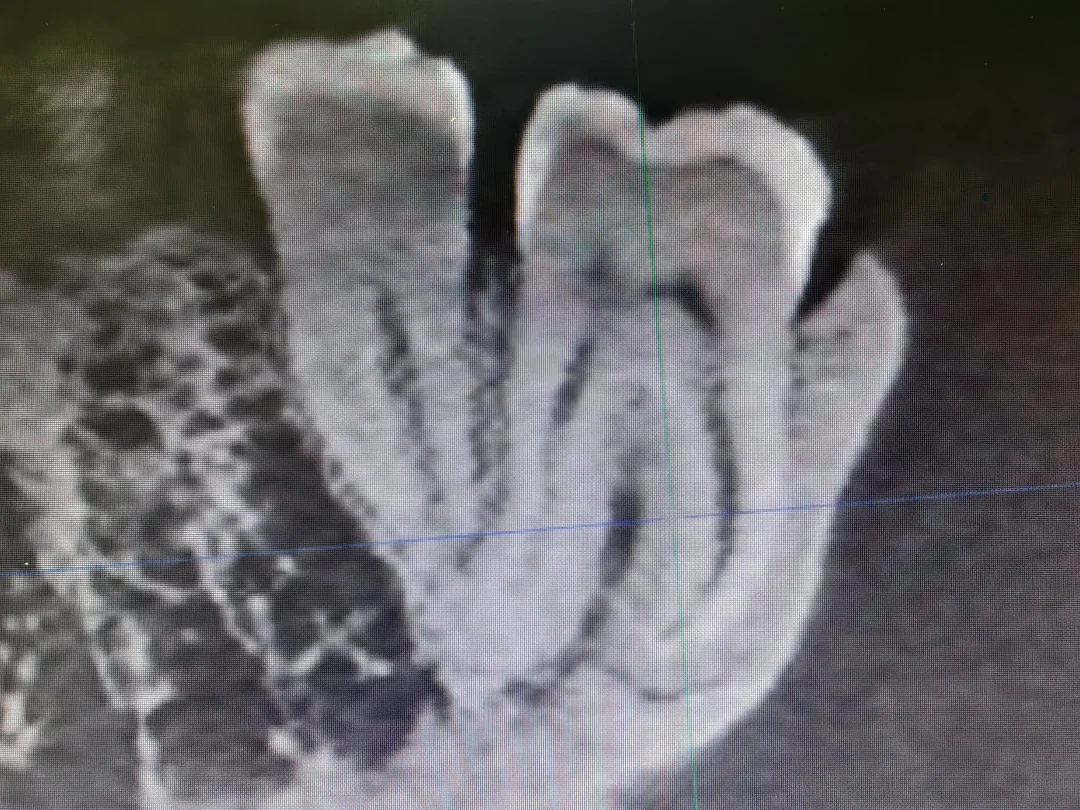

你以为的智齿VS实际上的智齿

今天终于让我用上了这张图片~ 在这个硕大无比的智齿年前,旁边那个大牙显得如此娇小可爱~ 本来我是不想拔这个牙的,可是想着人家来都来了, 就给人家拔了吧,结果这一拔就拔了一个小时~